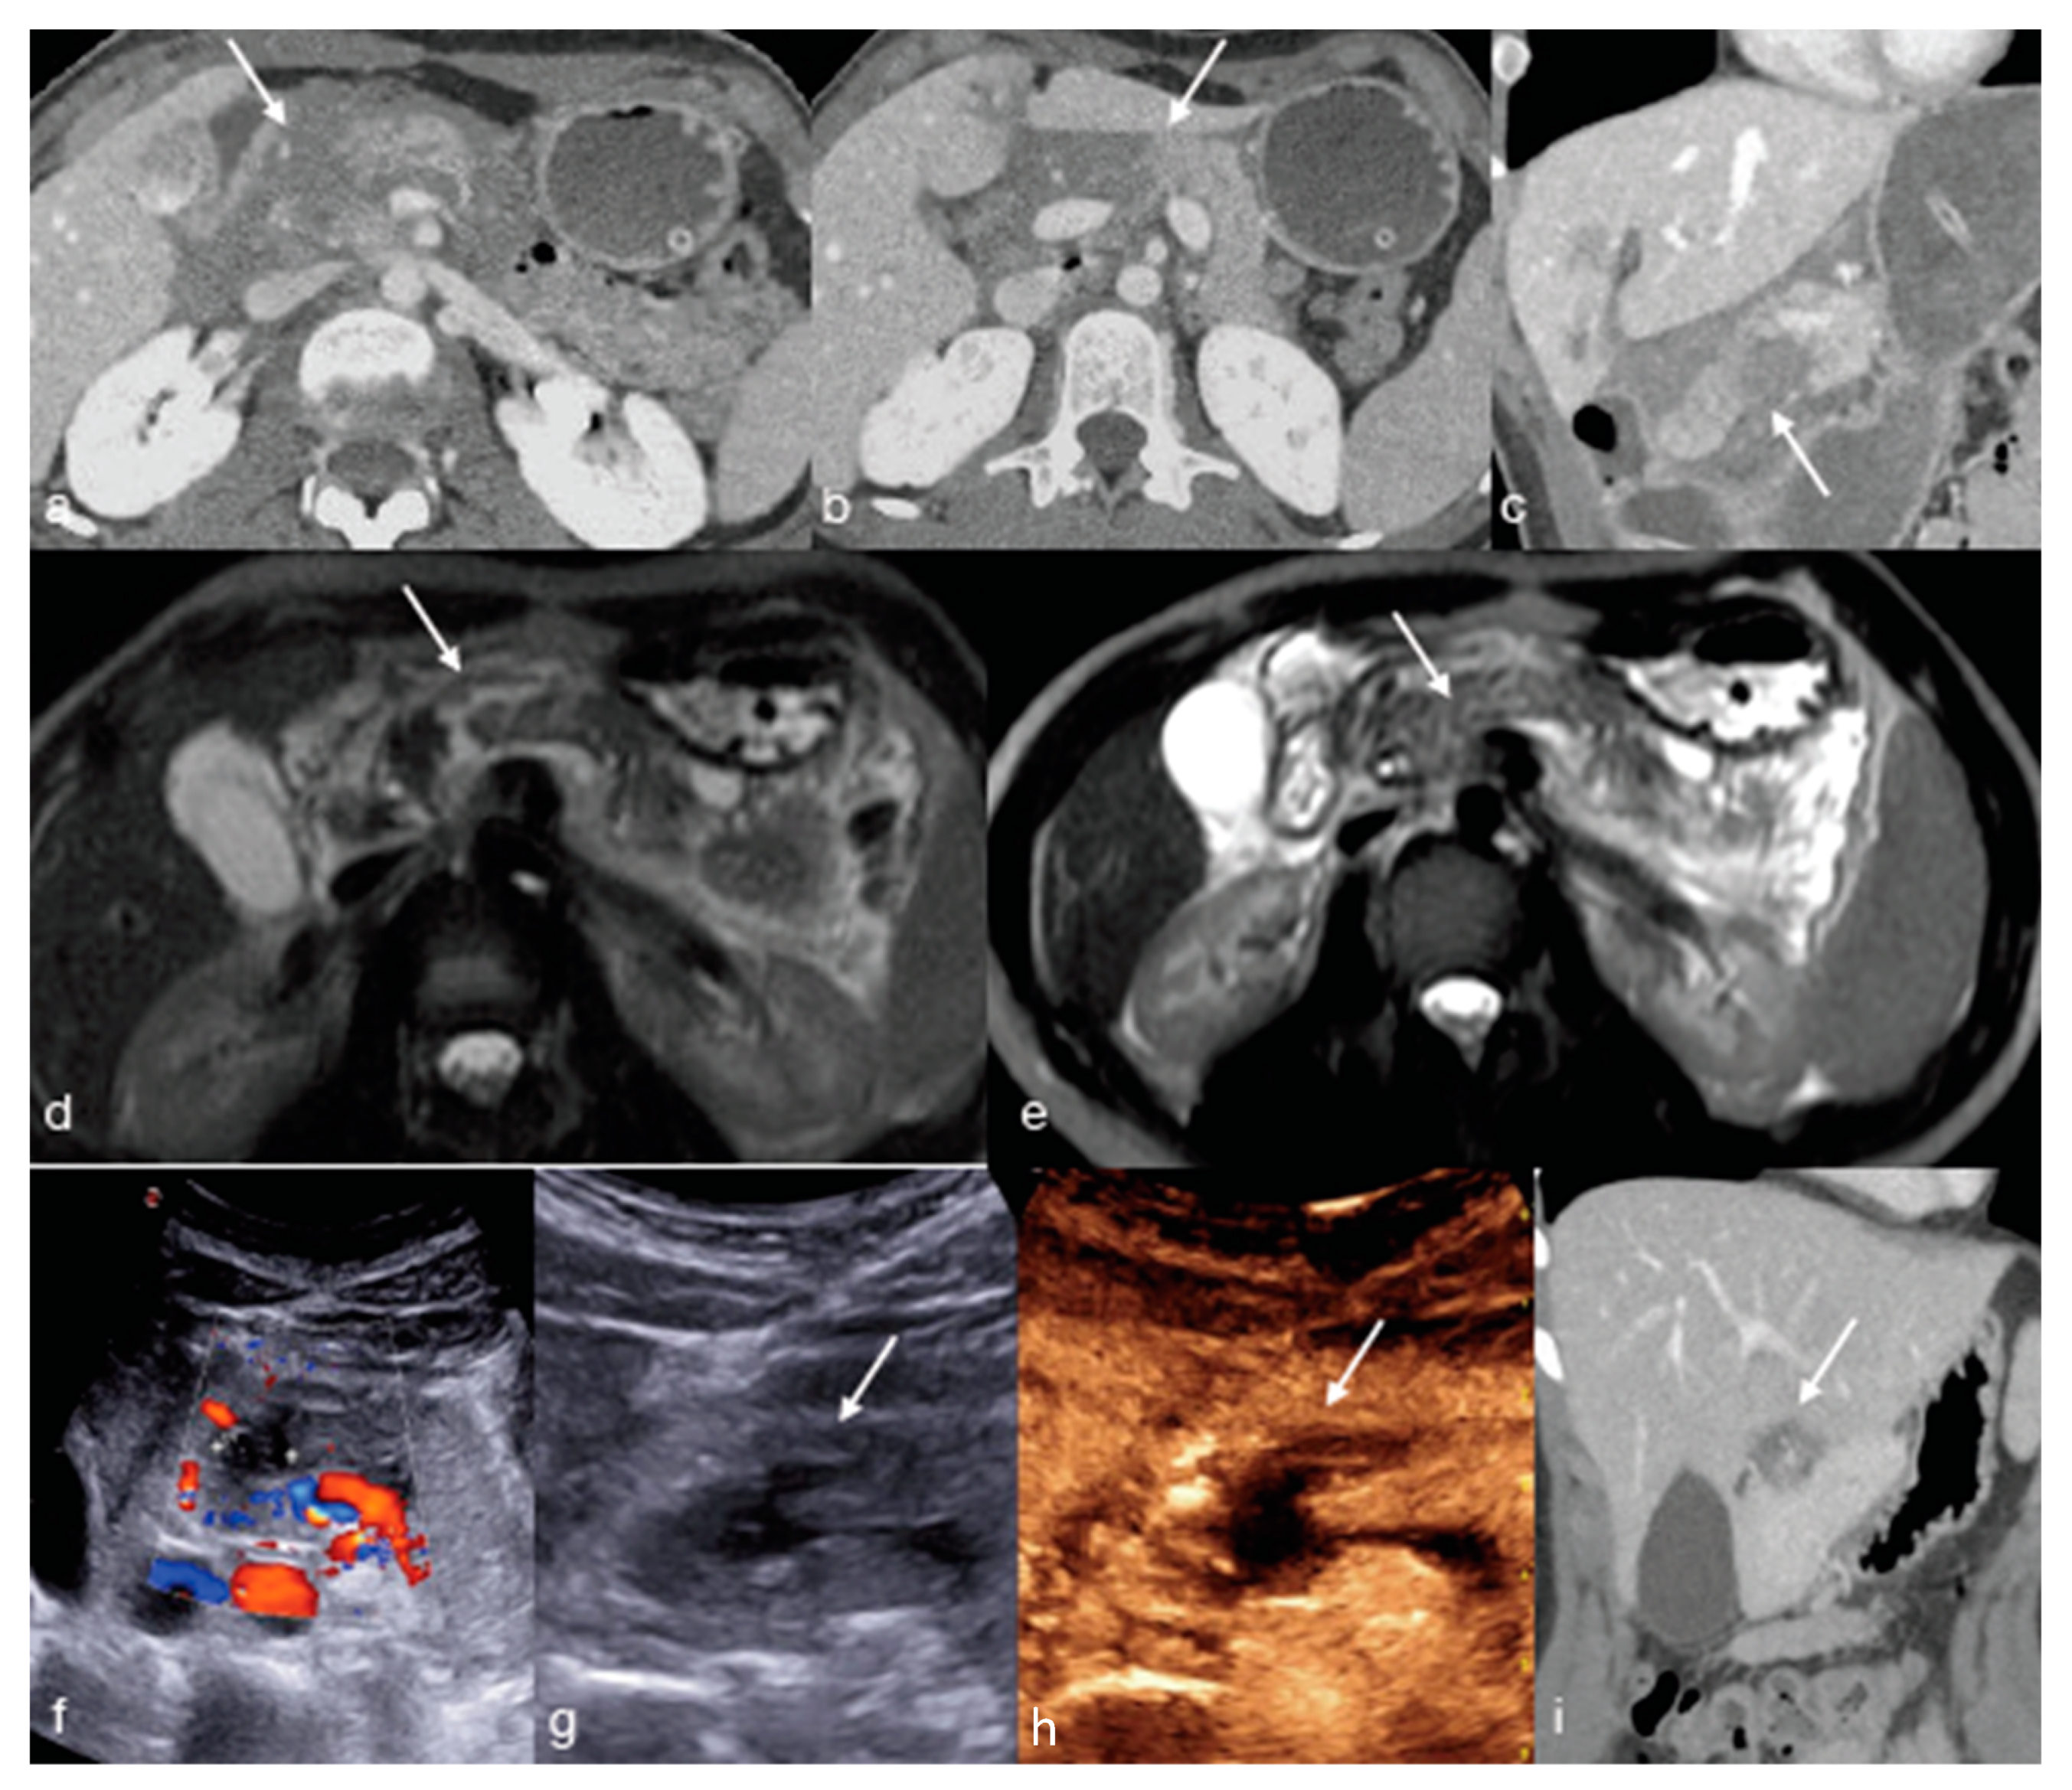

- Iacobellis, F.; Di Serafino, M.; Brillantino, A.; Mottola, A.; Del Giudice, S.; Stavolo, C.; Festa, P.; Patlas, M.N.; Scaglione, M.; Romano, L. Role of MRI in early follow-up of patients with solid organ injuries: How and why we do it? Radiol. Med. 2021, 126, 1328–1334. [Google Scholar] [CrossRef] [PubMed]

- Trinci, M.; Cirimele, V.; Ferrari, R.; Ianniello, S.; Galluzzo, M.; Miele, V. Diagnostic value of contrast-enhanced ultrasound (CEUS) and comparison with color Doppler ultrasound and magnetic resonance in a case of scrotal trauma. J. Ultrasound 2019, 23, 189–194. [Google Scholar] [CrossRef] [PubMed]

- Miele, V.; Piccolo, C.L.; Sessa, B.; Trinci, M.; Galluzzo, M. Comparison between MRI and CEUS in the follow-up of patients with blunt abdominal trauma managed conservatively. Radiol. Med. 2015, 121, 27–37. [Google Scholar] [CrossRef] [PubMed]